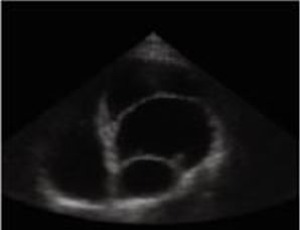

Abstract Pacemaker lead extraction is a challenging and potentially risky procedure, especially when dealing with leads that have been implanted for a long period of time [1]. In this case report, we present a 45-year-old patient who required the extraction o.....